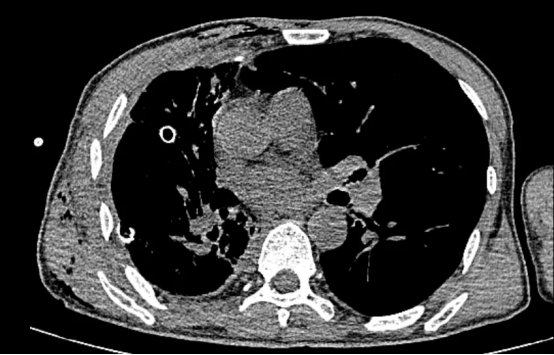

术前影像(左右滑动查看更多)

该患者为61岁男性,肺部病情错综复杂。4年前确诊肺结核后因治疗不规范,发展为“利福平耐药”结核,病情持续恶化。2年来反复咯血,虽经3次支气管动脉栓塞术暂时控制,但病灶顽固,收治入院时已形成多重诊断:毁损肺(右上)、右肺下叶鳞癌(背段)、肺曲霉菌病、陈旧性肺结核。其右肺上叶完全丧失功能,并与胸壁形成致密粘连,医学上称为“毁损肺”——胸外科领域公认的极高难度手术。